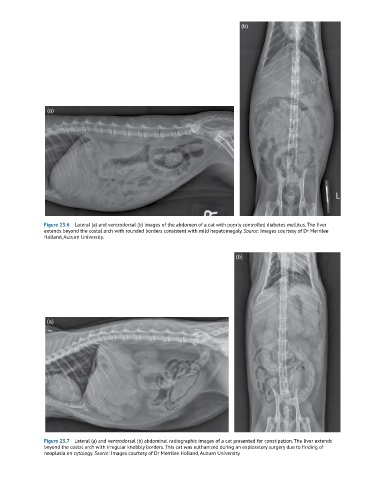

Figure 23.6 Lateral (a) and ventrodorsal (b) images of the abdomen of a cat with poorly controlled diabetes mellitus. The liver

extends beyond the costal arch with rounded borders consistent with mild hepatomegaly. Source: Images courtesy of Dr Merrilee

Holland, Auburn University.

Figure 23.7 Lateral (a) and ventrodorsal (b) abdominal radiographic images of a cat presented for constipation. The liver extends

beyond the costal arch with irregular knobbly borders. This cat was euthanized during an exploratory surgery due to finding of

neoplasia on cytology. Source: Images courtesy of Dr Merrilee Holland, Auburn University.